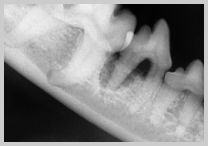

Radiograph of 408 with advanced

attachment loss of caudal root. This four walled pocket or

"cup lesion" carries a poor prognosis